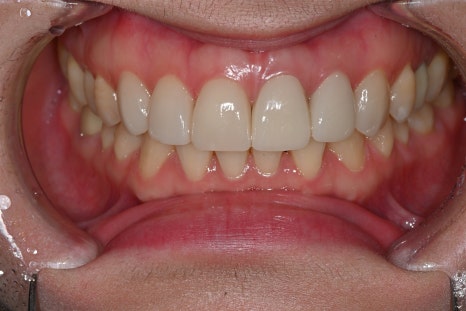

OBZERO treatment involving crown remakes

In this case, a total of 6 areas were designed.

OBZERO Pure has excellent reproduction under natural light,

and zirconia crowns offer high strength and color stability,

making it a combination that can achieve both anterior function restoration

and esthetics.

- Rechecking the tooth condition after removing the existing crown

To resolve discoloration and border issues, the existing restoration was removed,

and the gum line and tooth shape were newly designed.

- Shaping and scanning 4 abutments for OBZERO Pure laminate

Within the possible range, the amount of reduction was minimized,

and the exact form was captured with an intraoral scanner.

- Designing 2 anterior crowns and taking impressions

The central axis of the front teeth and the bite height were accurately established.

- Checking function, speech, and esthetics after placing temporary teeth

We carefully checked the patient’s speaking habits,

the smile line, and air leakage during speech.

- Final restoration placement and OBZERO setting

On the day of treatment, after adjusting the overall bite, color, and gloss,

permanent bonding was completed.

- One-week follow-up check

We checked bite stability and gum adaptation,

and confirmed good results in all areas.